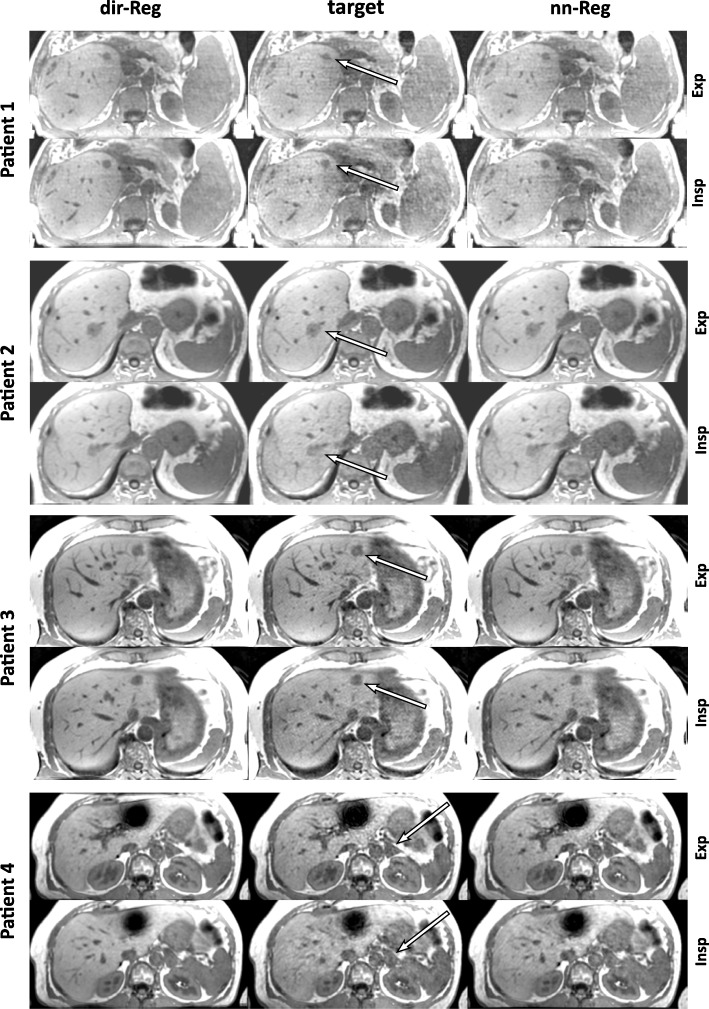

Mean scores of the blinded reading of the patient data sets are displayed in Fig. 6. Expiration and inspiration target scores are lower in all criteria compared with both registration schemes. Noise and overall image quality are rated higher for dir-Reg than nn-Reg. The structure delineation of the registration schemes was rated equally. Inspiration dir-Reg scores are higher in all categories compared to nn-Reg. Corresponding expiration rating is higher than inspiration for the target and nn-Reg whereas dir-Reg structure and overall image quality scores are higher and noise the same. Over all categories, mean expiration scores were 2.92 ± 0.18 for the target, 3.19 ± 0.22 for nn-Reg and 3.56 ± 0.14 for dir-Reg and mean inspiration scores 2.25 ± 0.12 for the target, 2.72 ± 0.04 for nn-Reg and 3.78 ± 0.04 for dir-Reg. The patient images in Fig. 7 exemplarily visualize these findings. The artifacts in the lower patient images were caused by metal clips. Dir-Reg images show a more homogeneous signal compared with nn-Reg and especially with the target. In the case of inspiration, the image quality of the target and nn-Reg images strongly decreases compared to dir-Reg images.

Fig. 7.

Exemplary transversal slices of the registered and target image sets for each patient containing a lesion (arrows). Expiration and inspiration images are displayed for comparison. The arrows illustrate the inferior image quality of the target image sets